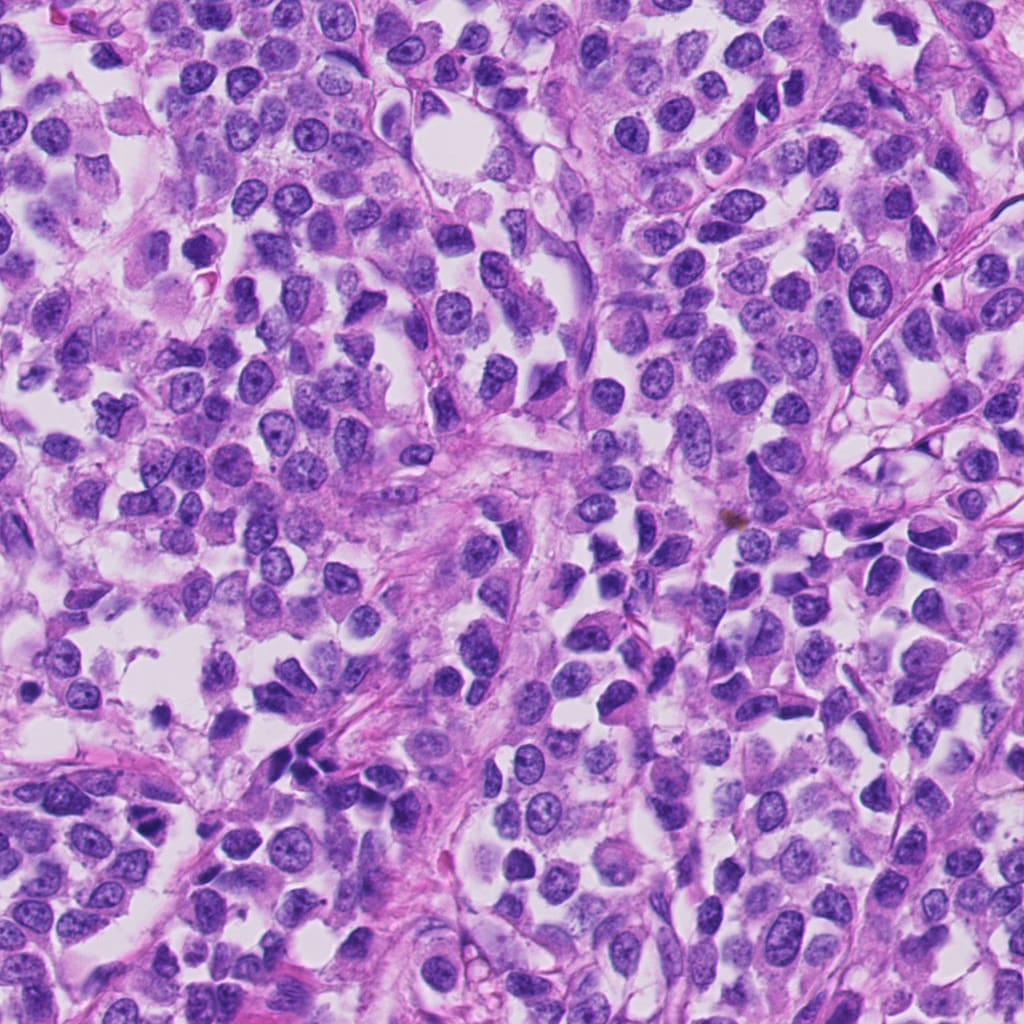

(c) original patch from Hamamatsu S360

Refer to caption

(d) transformed patch for Hamamatsu S360

(e) original patch from Aperio ScanScope CS2

(f) transformed patch for Aperio ScanScope CS2

(g) original patch from Leica GT450

(h) transformed patch for Leica GT450

Figure 2: The plots show 1024x1024 patches from original and transformed patches. The domain variability is evident by visual differences in staining in (a), (c), (e), and (f). The transformed patches to the right (b), (d), (f), and (h) respectively shows consistent staining pattern while preserving morphology.